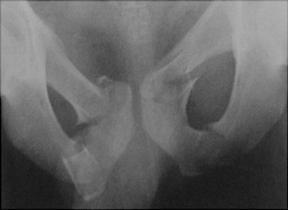

Disjunctie de simfiza pubiana Disjunctie

de simfiza pubiana

Disjunctie sacro-iliaca stanga Disjunctie sacro-iliaca stanga. Aspect CT